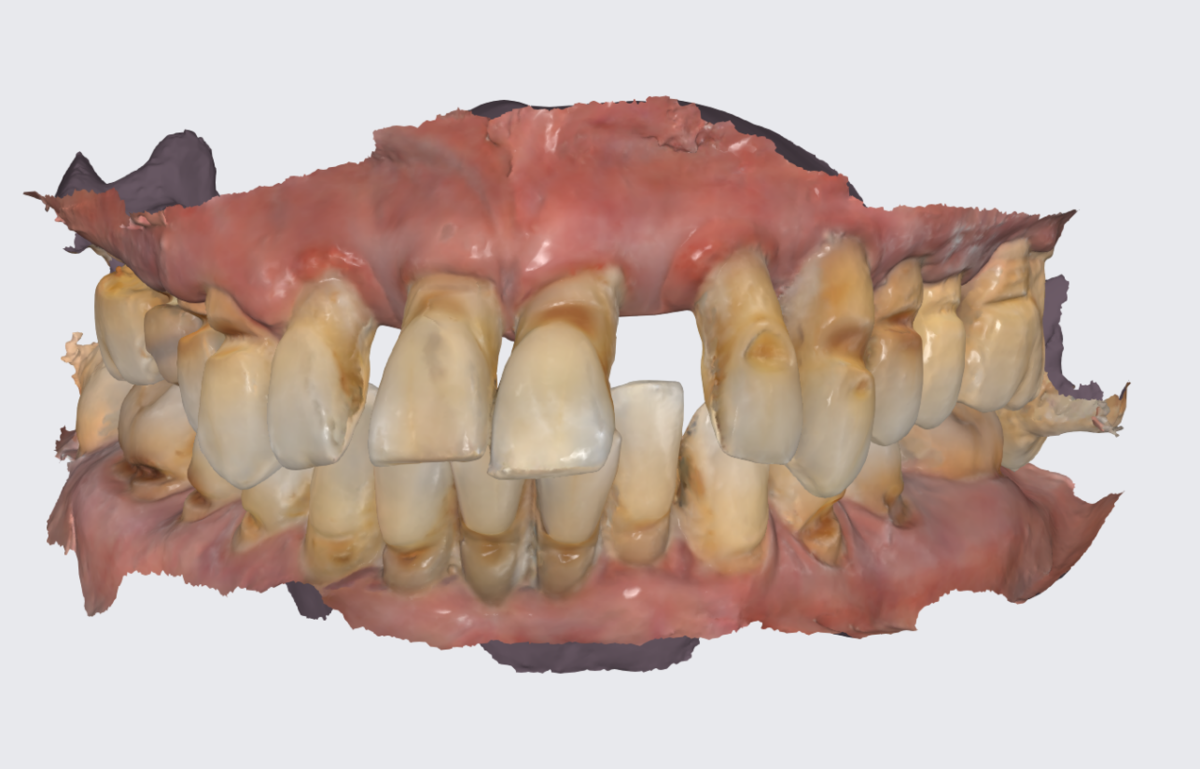

Цифровой слепок верхней челюсти.

Задача - восстановить жевательную эффективность во втором сегменте верхней челюсти.

Кажется, что всё просто.

Прикус. Мезиальный. Нижняя челюсть впереди верхней.

Мезиальный прикус.